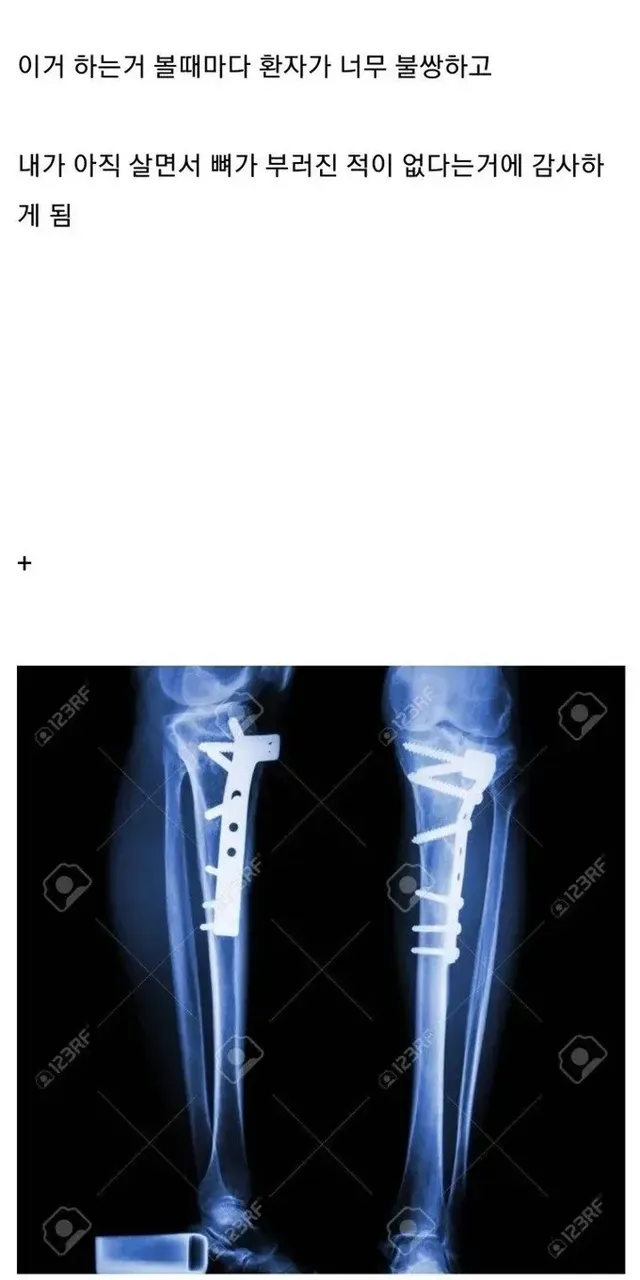

[스압] 뼈 안 부러져본 사람들이 의외로 모르는 사실,,